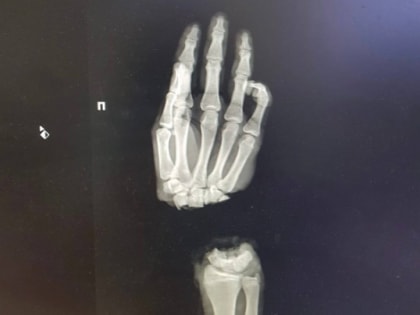

Врачам Университетской клиники ПИМУ в Нижнем Новгороде удалось сохранить отрубленную кисть руки 16-летнему пациенту.